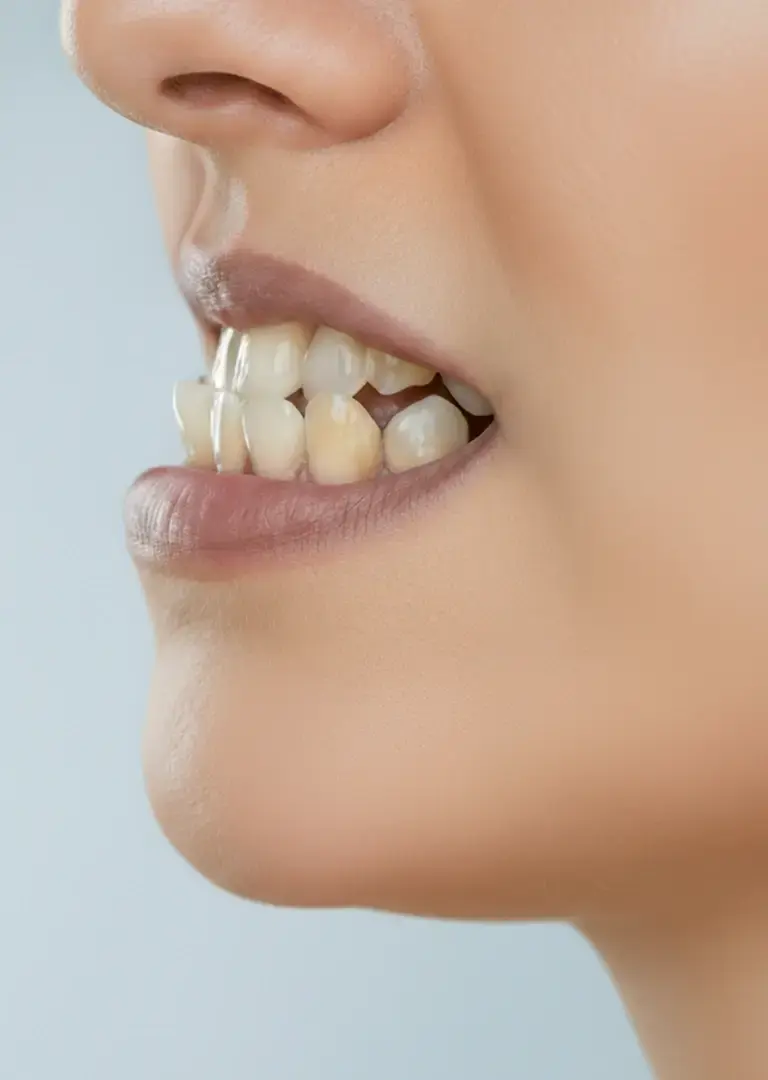

Мезиальный прикус или прогения — аномалия, при которой нижняя челюсть и зубы выступают вперед относительно верхних. Со стороны лицо имеет «волевой» или «упрямый» профиль, так как нижняя треть лица визуально более массивная.

Симптомы мезиальной окклюзии: Вид сбоку: массивный, выступающий вперед подбородок. Нижние зубы перекрывают верхние, формируя так называемое обратное смыкание. Вид спереди: «вогнутый» профиль лица, западение верхней губы. Происходит нарушение контакта между передними зубами и появляются проблемы с откусыванием пищи.

мезиальный прикус